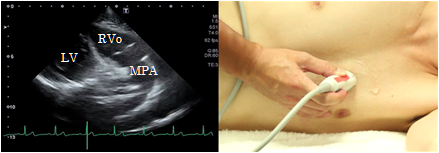

Longitudinal view of the right ventricular outflow tract

To obtain a longitudinal view of the right ventricular outflow tract, rotate the probe slightly in a counterclockwise direction from the position showing the aortic level of the short axis view of the left ventricle and tilt it so that the ultrasound beam is directed slightly outwardly. This view is suitable for the determination of wall motion abnormalities of the right ventricular outflow tract, stenosis of the right ventricular outflow tract, and pulmonary valve stenosis.